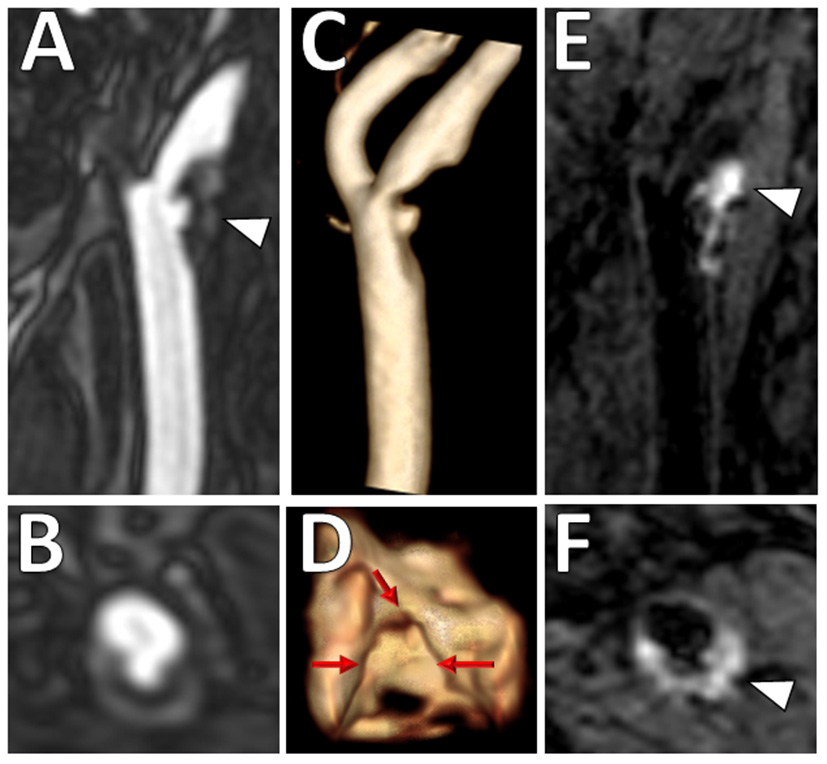

Figure 2

Intraplaque hemorrhage in carotid plaque on Magnetization-Prepared Rapid Gradient Echo (MPRAGE) and Time-of-flight MR angiography (TOF MRA). T1 hyperintense IPH at the right carotid bifurcation (white arrowheads) on both (A) MPRAGE and (B) TOF MRA. The MPRAGE image has fat and blood flow suppression, allowing for the IPH to standout in contrast to the vessel lumen and surrounding soft tissues. The TOF MRA image also demonstrates an intact hypointense fibrous cap at this level (black arrowhead).

Physiologically, the fibrous cap refers to a layer of fibrous connective tissue that contains macrophages and smooth muscle cells, which if ruptured, exposes the adjacent LRNC to luminal blood resulting in activation of the thromboembolic cascade. It has been shown that thin or ruptured fibrous cap is associated with increased risk of ischemic stroke (27, 28, 34). One of the key advantages of MRI is that it can assess fibrous cap status with contrast-enhanced T1W sequences and 3D time-of-flight magnetic resonance angiography (TOF MRA) (11). On contrast-enhanced T1W sequences, normal thick fibrous cap shows smooth linear enhancement overlying the plaque, whereas on TOF MRA, uniform hypointense band between bright lumen and gray plaque core is present (22, 24). An example is shown in Figure 2B. Presence of an irregular and disrupted fibrous cap is associated with ipsilateral ischemic stroke, most commonly due to a thromboembolic mechanism (35). However, this feature can be more difficult to assess than other features in clinical practice.

Luminal surface morphology of carotid plaques can be classified as smooth (no irregularity/ulceration), irregular (surface fluctuates from 0.3 to 0.9 mm), or ulcerated (cavities measuring ≥1 mm) (36). Both irregular and ulcerated carotid plaque surfaces are associated with increased risk of stroke (36, 37). An example is shown in Figure 3. On MRI, luminal evaluation is possible with contrast-enhanced MRA (38, 39). MRI can detect carotid plaque ulcerations with similar sensitivity to CTA and the use of contrast-enhanced MRA is preferred over unenhanced TOF MRA due to reduced flow artifacts (38).

Figure 3

Ulcerated plaque with intraplaque hemorrhage on VW-MRI. Male patient presented with clinical and imaging evidence of a 1–2-year history of recurrent left MCA territory infarcts. (A,B) Contrast-enhanced MRA neck confirmed a left cervical carotid bifurcation stenosis with an ulcerated plaque (A, arrowhead). (C,D) 3D surface volume rendering of the left carotid plaque depicts the ulcerated surface morphology with (D) axial image through the ulceration showing marked surface irregularity (red arrows). (E,F) Carotid VW-MRI showed intraplaque hemorrhage (arrowheads), depicted as T1 hyperintense signal on a fat-suppressed T1W MPRAGE image. Based on the clinical and imaging findings, the patient underwent a left carotid endarterectomy.